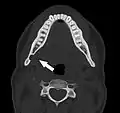

Stafne bone cavity seen on axial CT